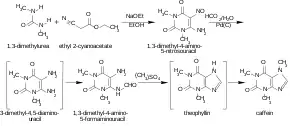

Caffeine may be synthesized in the lab starting with dimethylurea and malonic acid.[200][201][205]